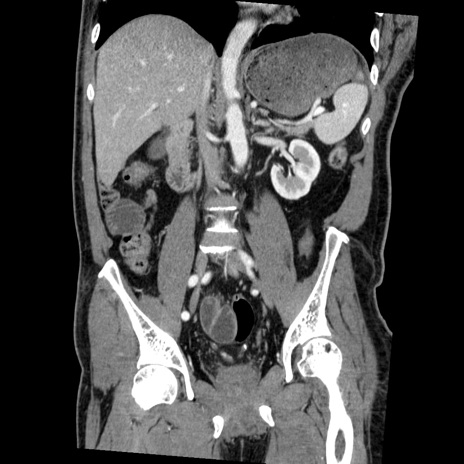

症例22(冠状断像)

【症例】50歳代男性

【主訴】腹痛

【現病歴】AVMからの被殻出血のため回復期リハ病棟入院中。 本日午後3時頃急に下腹部痛が出現した。

【既往歴】AVM、被殻出血、虫垂炎、高血圧

【身体所見】意識晴明、左半身不全麻痺、会話の理解は良好、36.5°C、腹部:膨隆、全体に板状硬、下腹部正中に圧痛点あり、反跳痛-、筋性防御不明、右下腹部にope scar

【データ】WBC 9400、CRP 0.06